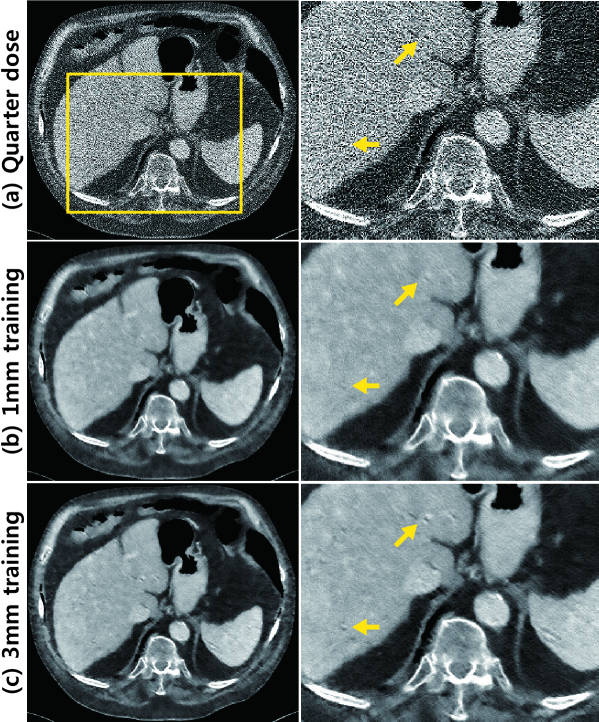

Refer to caption

Figure 6: Reconstruction results from the training data ‘L291’: (a) routine-dose image, (b) quarter-dose image, and the results with (c) the proposed network trained with 1mm slices followed by 3mm averaging, and (d) the proposed network trained with 3mm slices. The second column shows enlarged images from the yellow boxes. Yellow arrows denote the image details. The intensity range was set to (-160,240) [HU].

Figure 7: Reconstruction results from the test data ‘L031’: (a) quarter-dose image, and the results by (b) the proposed network trained with 1mm slices followed by 3mm averaging, and (c) the proposed network trained with 3mm slices. The second column shows enlarged images from the yellow boxes. Yellow arrows indicate the image details. The intensity range was set to (-160,240) [HU].

First, the comparative results from the 1mm and 3mm training data are shown in Fig. 6 and Fig. 7. The denoised images through the newly trained network with 3mm images preserve the fine image details better than those of the previous network. In particular, the image edges, such as the boundaries and details of the organs, become clearer. Although the denoised images, trained with 1mm slices, retained the details of the regions with lesions and significantly suppress the streaking artifacts, we found that the denoised images appeared somewhat blurred and that some high-frequency textures were often lost. This limitation resulted from the fact that the normal-dose CT images with a thickness of 1mm also contain noise, which reduces the accuracy of the supervised learning process.